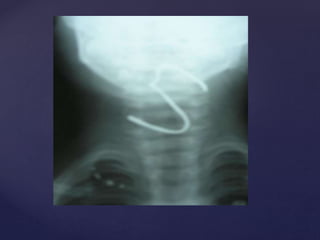

 Plain X ray Skull Lateral View R

and L showing fracture.

 Diagnosis: #Nasal Bones.

 Treatment : Correction under GA.